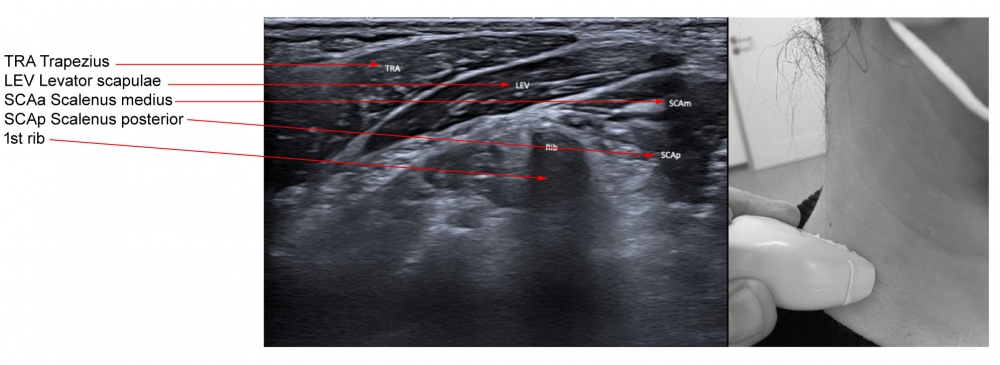

Scalenus medius is the largest muscle of the scalenus group, and arises from the transverse processes of the cervical vertebrae and inserts into the superior portion of the first rib. This muscle can elevate the first rib or bend and rotate the neck. A needle can be placed into the scalenus medius muscle by palpating the belly of the muscle, in the floor of the posterior triangle, two finger breadths anterior to the anterior border of the trapezius muscle. At this point the muscle is just beneath the skin. The upper portion can be inserted by placing the needle just anterior to the lateral edge of the splenius capitis muscle to a depth of 1.5 to 3.0 cm.

Scalenus posterior arises from the posterior portion of the transverse processes of C5–6, passing medially and posteriorly to the scalenus medius, and inserts into the outer surface of the second rib, deep to the attachment of the serratus anterior. The scalenus posterior elevates the second rib or bends and slightly rotates the neck.

Figure 7. Trajectory of approach and relationships of the surrounding muscles to scalenus